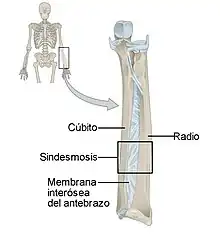

Son aquellas en que los extremos de los huesos están unidos por tejido fibroso. Este tipo de articulaciones tienen muy poca movilidad. Un ejemplo de articulación fibrosa son las suturas que unen los huesos del cráneo. Un tipo particular de articulación fibrosa es la sindesmosis en la que dos huesos se unen mediante una lámina de tejido fibroso, como ocurre en la membrana interósea del antebrazo que une el cúbito con el radio. Un caso particular es la sindesmosis dentoalveolar, también llamada gonfosis, que es una articulación fibrosa, sin movimiento en condiciones normales, que se establece entre la raíz de una pieza dental y la apófisis alveolar situada en la mandíbula.[7]